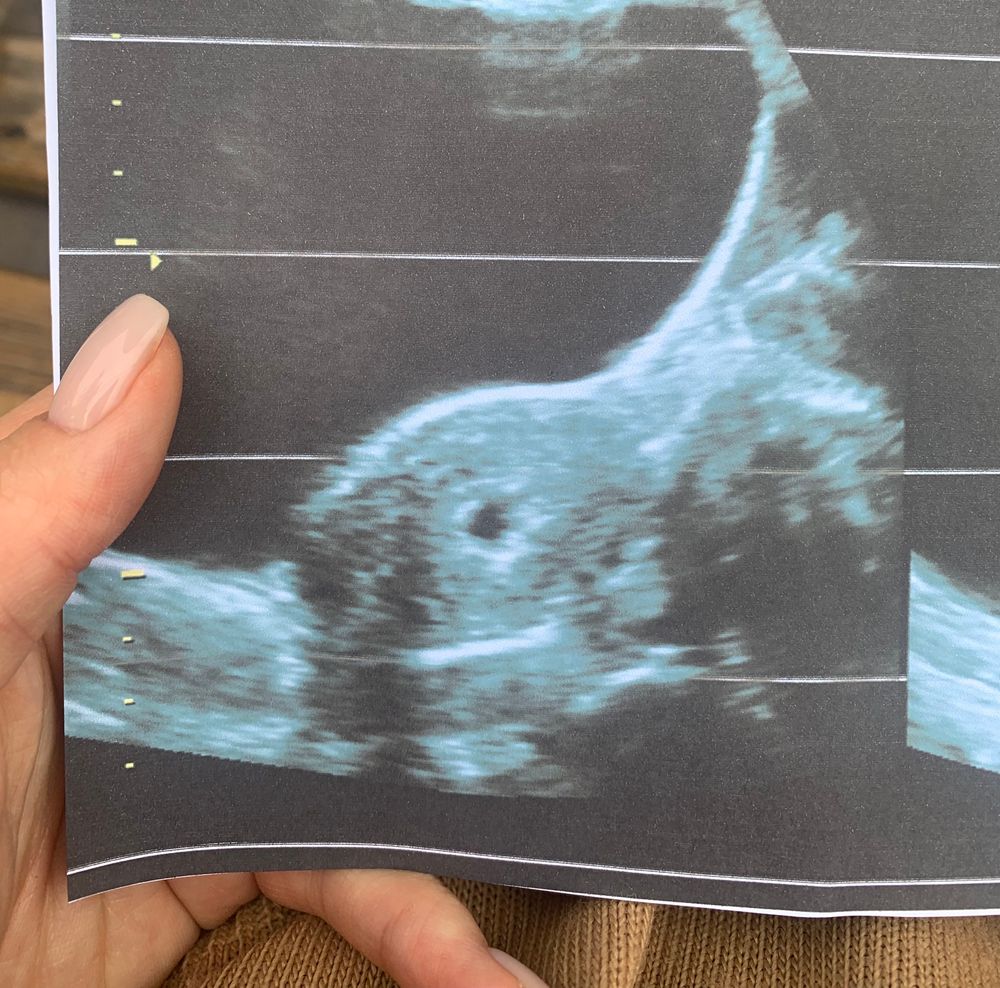

Первое узи 🥰